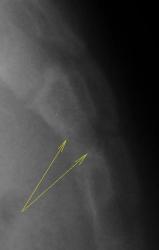

Ребенок направлен хирургом на рентгенографию крестца и копчика, Накануне ребенок упал. Приводится только боковая рентгенограмма, так как рентгенограмма, выполненная в прямой проекции не информативна.

Вопрос. Есть перелом или нет перелома?

?

Валентин Львович! Мне видится межпозвонковый промежуток. Смещение по ширине отсутствует. Возможно такой вариант развития. Все таки изолированно сломать крестец у ребенка сложно.

Согласен с Ермолаевым, это межпозвонковый промежуток.